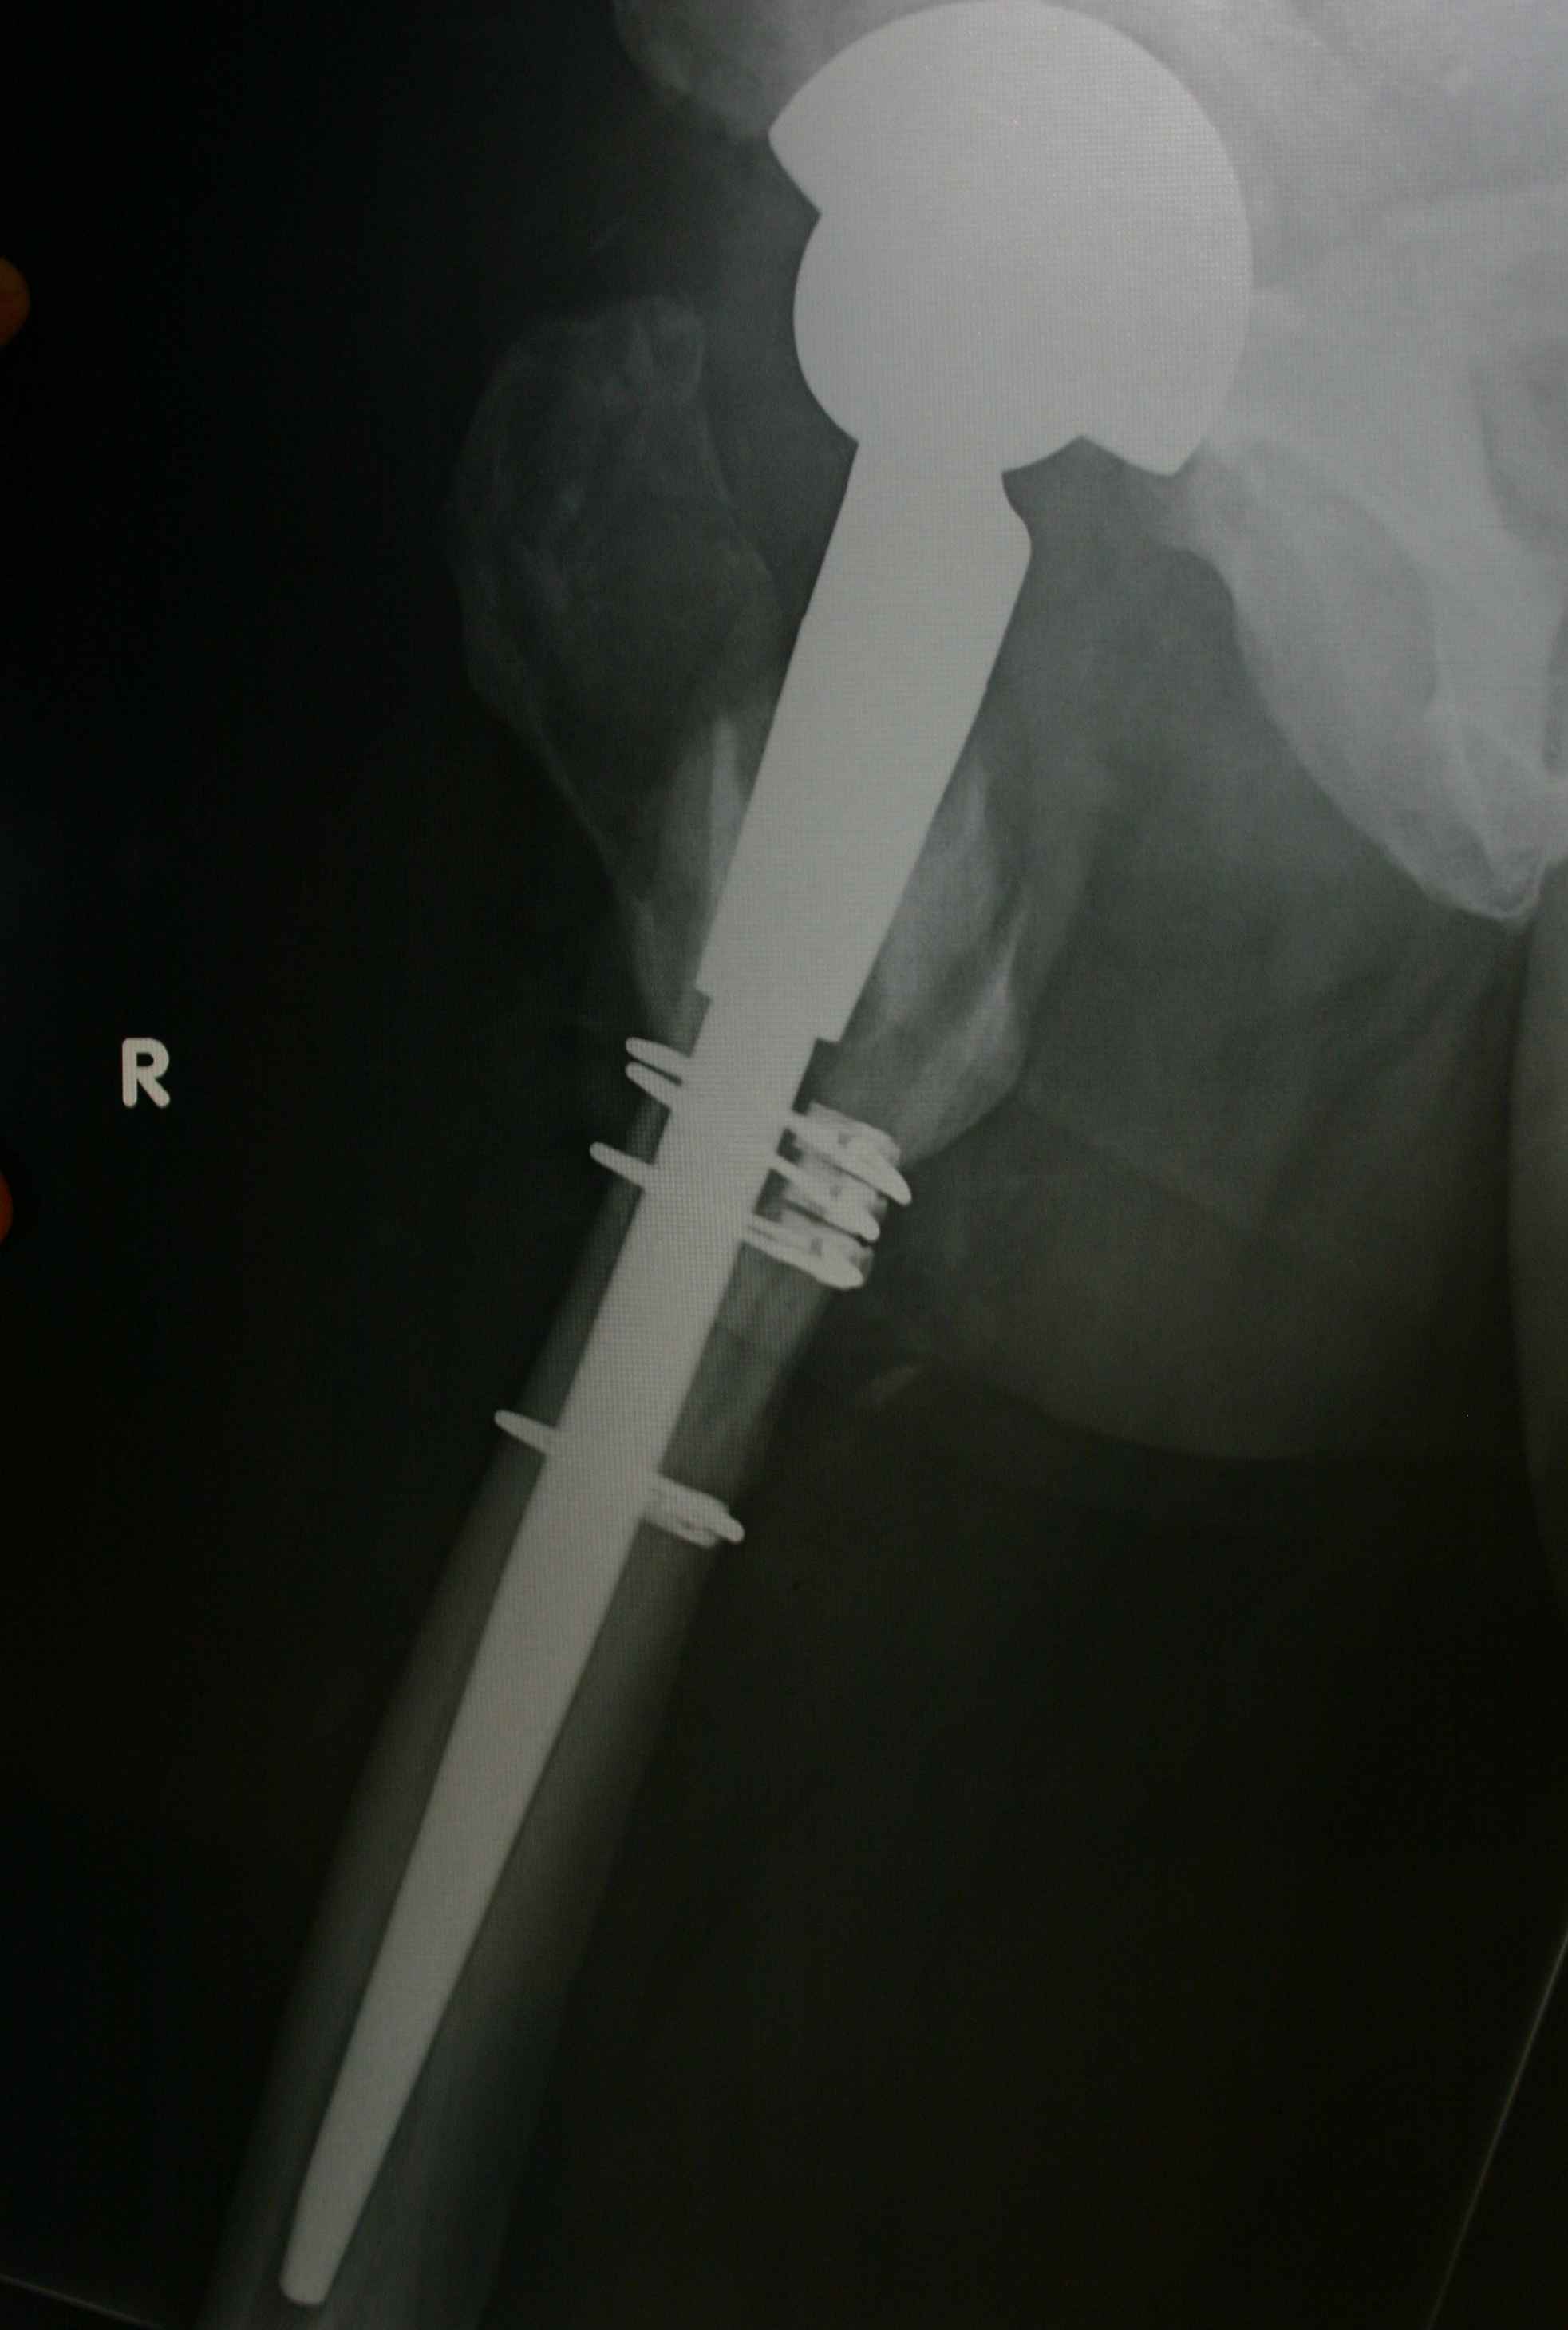

All of the participants had a total hip replacement on the right side, and they all took the driving test prior to having surgery. They were then randomly selected to repeat the test two, three or four weeks after hip replacement. Reaction time was measured by the computerised driving simulator.

I have driven after 4 weeks after most of my surgeries, I’ve had 7, but everyone is different. I had a femur fracture after my last surgery and couldn’t drive for 4 months.